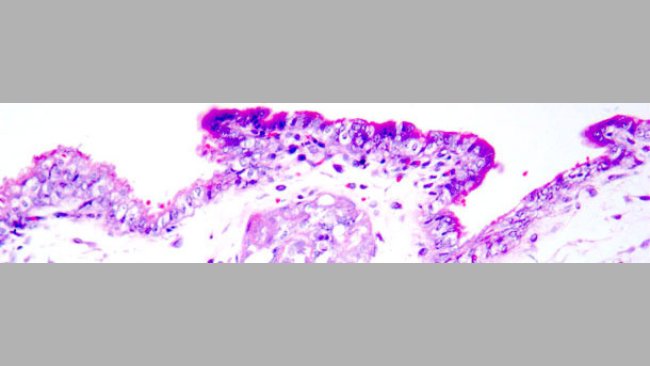

Łożyskowa transmisja cirkowirusa swiń typu 2.

Szczepienie loszek przeciw PCV2, poprzedzające inseminację nasieniem zanieczyszczonym PCV2 doprowadziło do ograniczenia wiremii, obniżenia siewstwa wirusa oraz ochrony płodów.